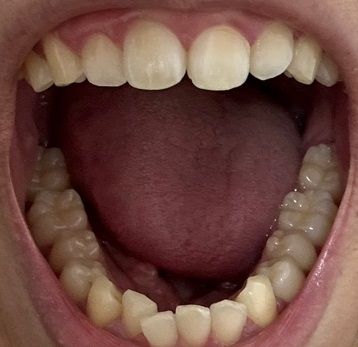

치아교정 해야될까요? 사랑니는 어떻게 해야할까요?

20대 후반 남성입니다. 충치 치료를 받아본 적은 없고, 위쪽의 오른쪽 사랑니 때문에

식사를 하다가 볼을 자주 씹게되고, 그래선지 몇달에 한 번씩 부은 적이 있습니다.

• 1번 째 사진